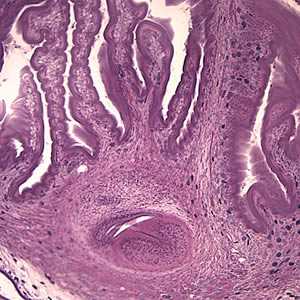

A 49-year-old male immigrant from Mexico was seen at a local medical facility specializing in neural disorders for frequent headaches and occasional seizures. Figures A and B show what was observed on a hematoxylin and eosin (H & E) stained section of lesions detected in the right frontal lobe of his brain. Figure A was taken at 40× magnification and Figure B was taken at 100× magnification. What is your diagnosis? Based on what criteria?

Figure A

- the extensive folding of the spiral canal and one sucker of the protoscolex (black arrow, Figure B).

- the presence of calcareous corpuscles (green arrows, Figure B).